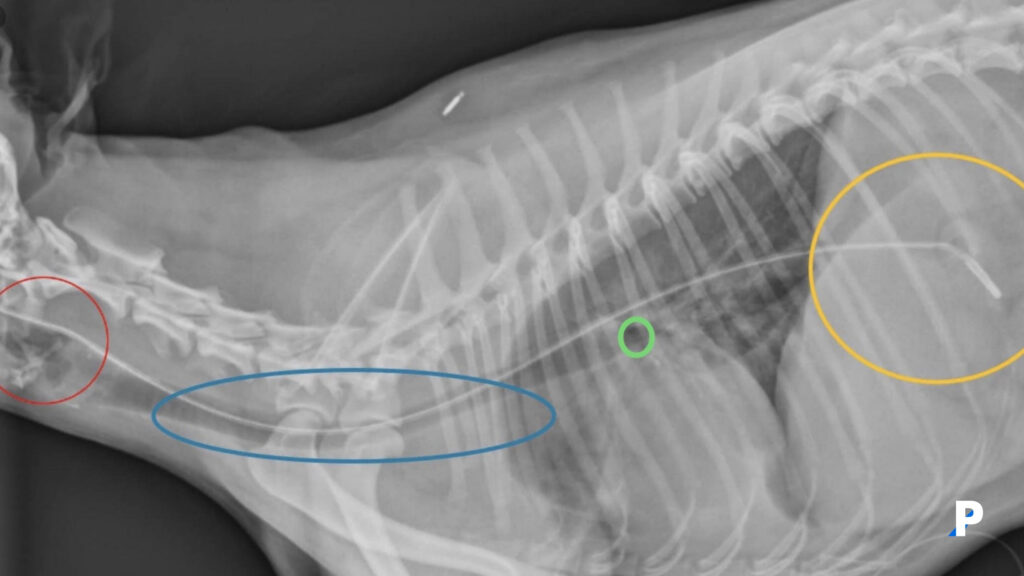

kedilerde yüksekten düşme sendromu belirtileri

Tüp ile beslenen bir kedinin yanal filmi